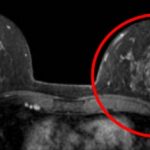

Voici une image d’IRM montrant un cancer.